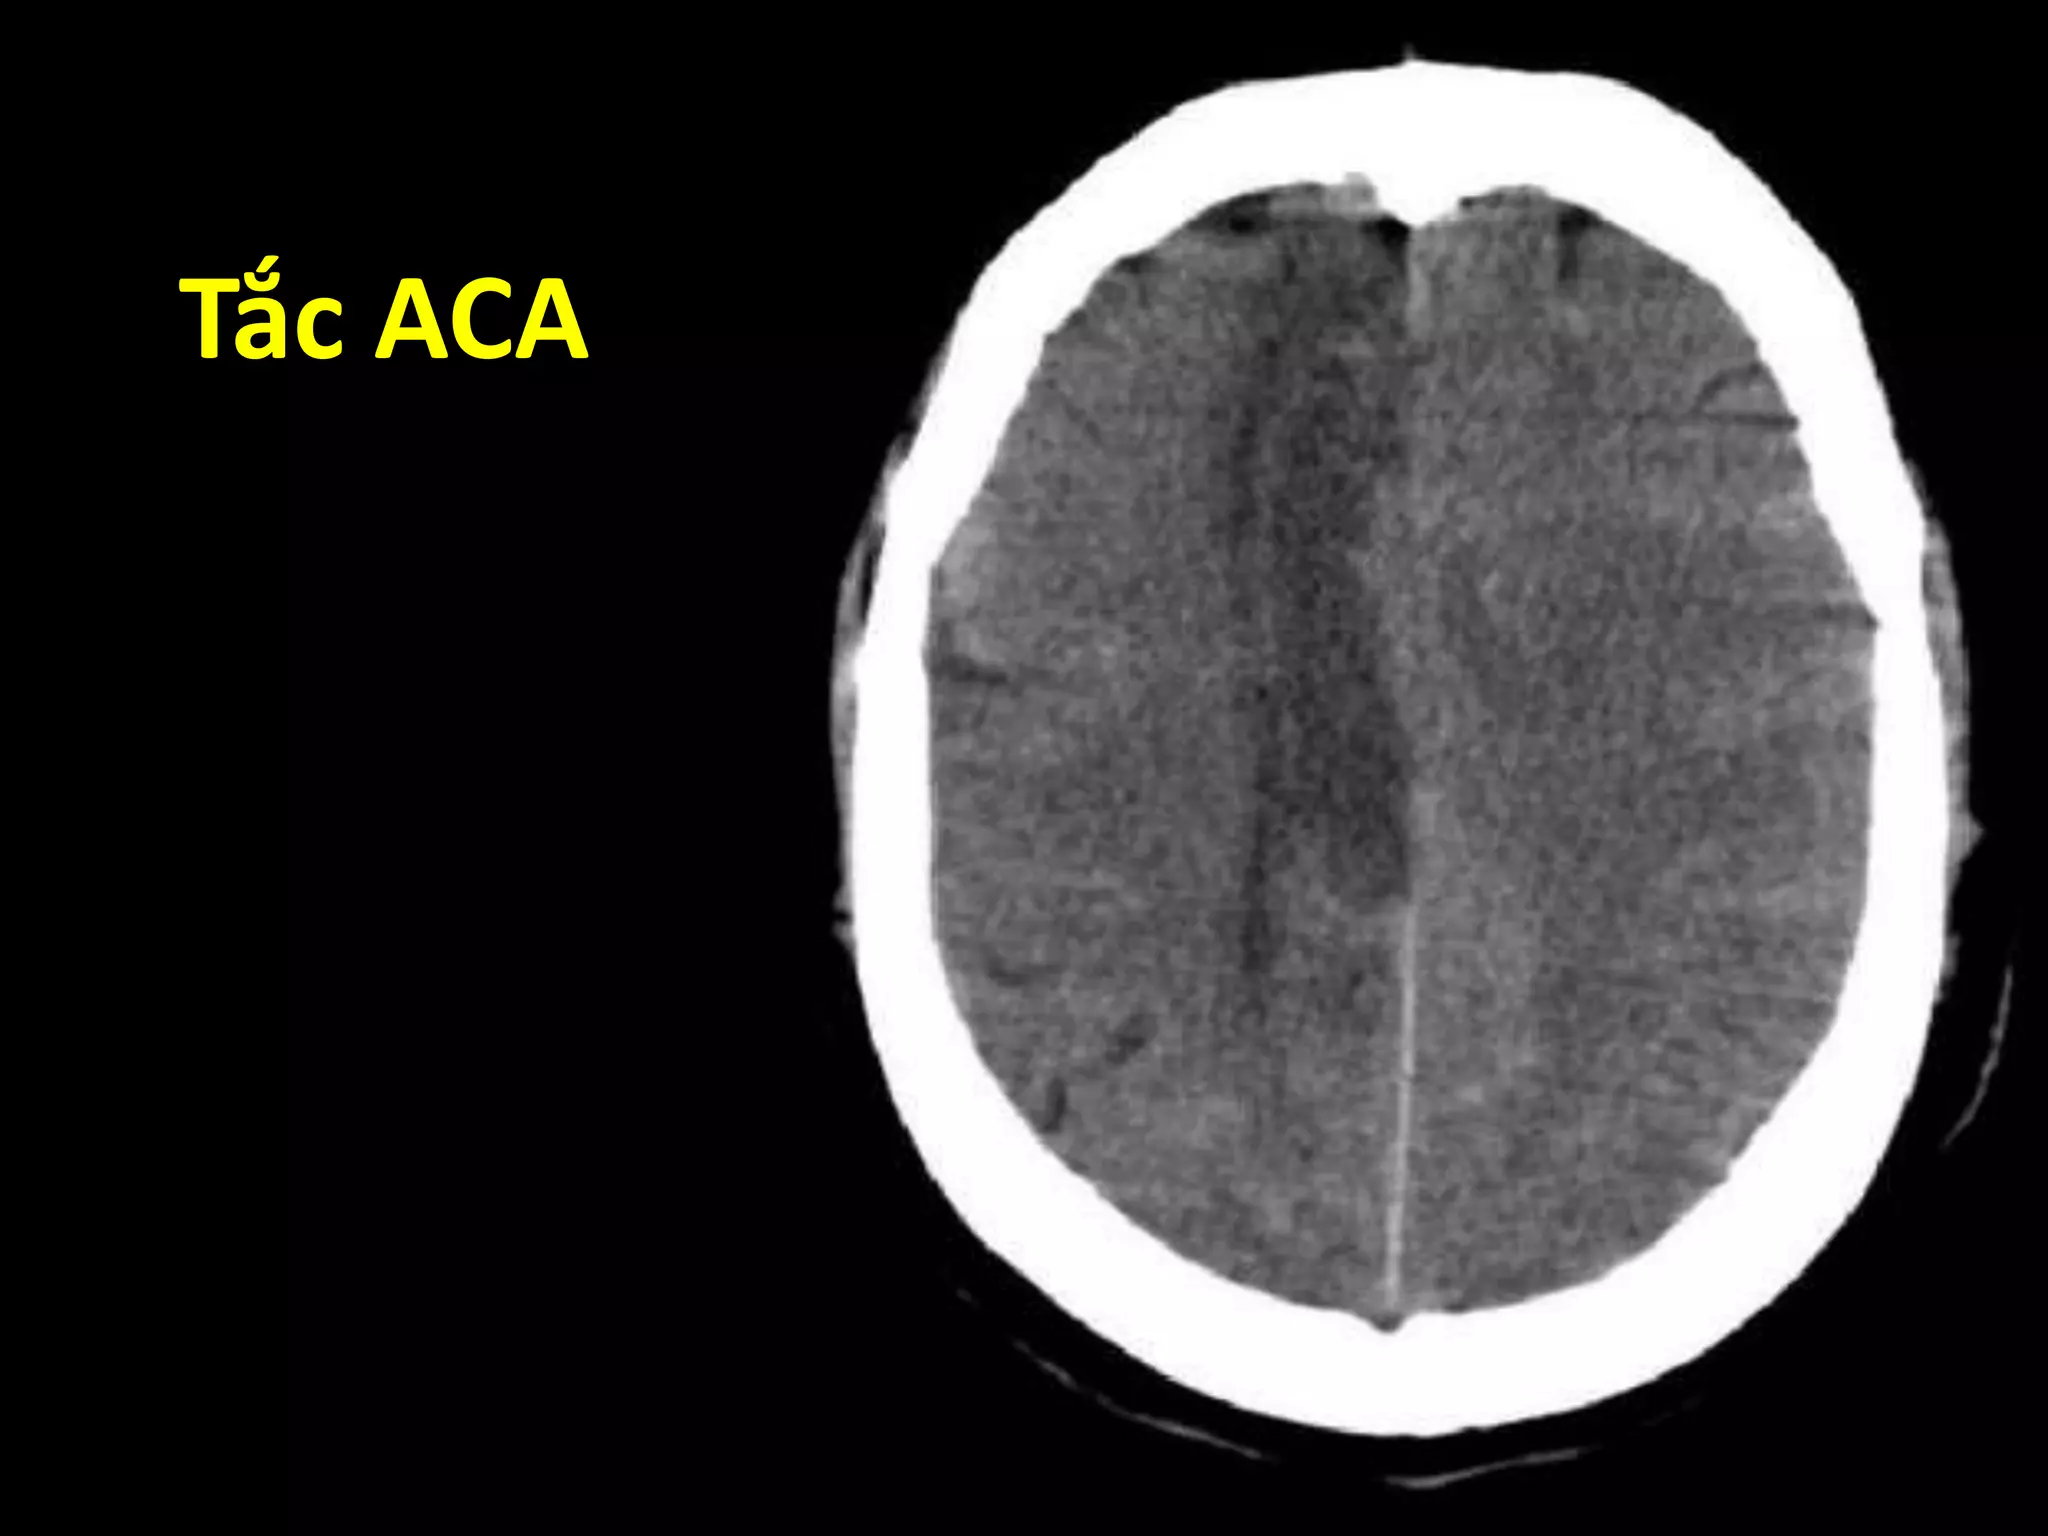

Vùng tưới máu

ACA MCA PCA

Nhìn trên Nhìn dưới

Tắc ACA

Tắc MCA

Tắc PCA